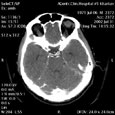

Отсутствие задней соединительной артерии виллизиевого круга. Отсутствие задней соединительной артерии виллизиевого круга

Пациент P., 55 лет

Отсутствие задней соединительной артерии виллизиевого круга.

ЦКБ5 Южной железной дороги, отделение лучевой диагностики.

Протокол.

На КТ-сканах в условиях ангиографического режима (ультравист 300 - 100,0) контрастированы сосуды виллизиева круга. Справа - отсутствие задней соединительной артерии.